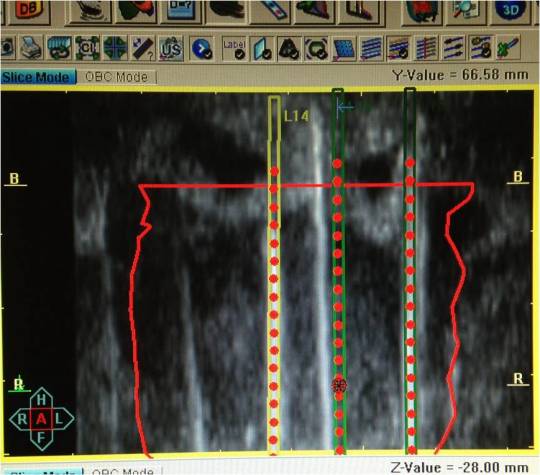

Производят

дозиметрическое планирование внутритканевой лучевой терапии. Первый этап –

введение в программу планирования информации о пациенте, физической информации

об источнике (активность), расчетной очаговой дозе. Далее полученные

изображения предстательной железы импортируются в планирующую программу. Второй

этап – стандартизация положения решетки, обведение контуров простаты, уретры,

прямой кишки, семенных пузырьков, при необходимости мочевого пузыря.

Планирование позиций интрастатов, составление «виртуального» дозиметрического

плана внутритканевого облучения (рис.2).